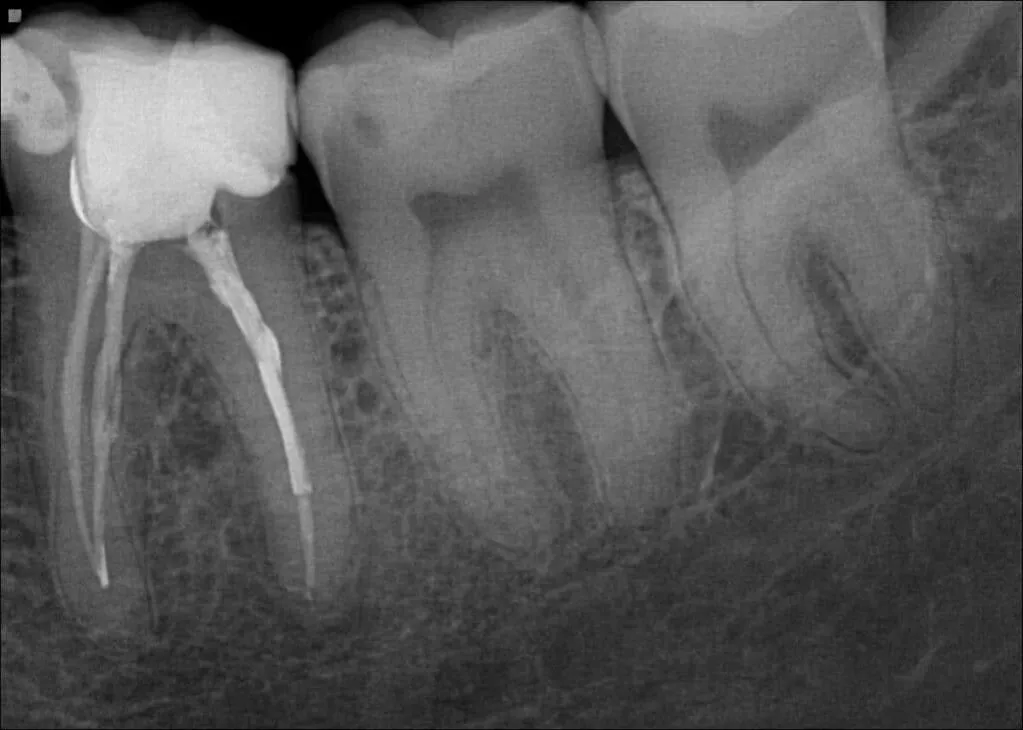

W trakcie leczenia kanałowego zdjęcia punktowe są nieocenione. Wykonujemy ich kilka przed rozpoczęciem leczenia, w trakcie (np. do kontroli długości kanałów) i po jego zakończeniu. Dzięki nim mogę precyzyjnie kontrolować postępy i upewnić się, że terapia przebiega prawidłowo, co jest kluczowe dla sukcesu leczenia.

Zdjęcie punktowe (zębowe), znane również jako zdjęcie wewnątrzustne, jest najczęściej wykonywanym badaniem. Służy do oceny 1-3 zębów, ich korzeni, otaczającej kości oraz tkanek przyzębia. Jest niezastąpione w diagnostyce próchnicy, stanów zapalnych okołowierzchołkowych czy kontroli leczenia kanałowego. Wiąże się z najniższą dawką promieniowania, co czyni je bardzo bezpiecznym i często stosowanym narzędziem.